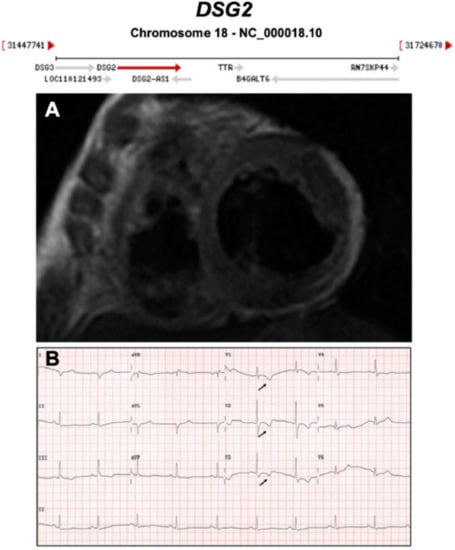

| DSG2 | Desmosome | 4–15% | AD | RV, LV, BIV | ARVC10 | 18q12.1; 16 | Frequent LV involvement, AR also reported | Definitive for ARVC |

3.1. Desmosomal Genes

- Chen, P.; Li, Z.; Yu, B.; Ma, F.; Li, X.; Wang, D.W. Distal myopathy induced arrhythmogenic right ventricular cardiomyopathy in a pedigree carrying novel DSG2 null variant. Int. J. Cardiol. 2020, 298, 25–31. [Google Scholar] [CrossRef] [PubMed]